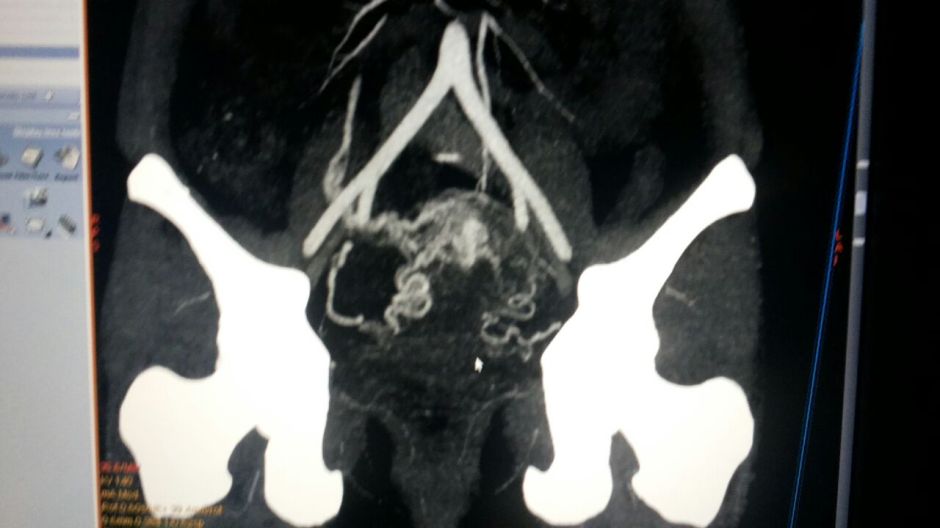

The Contrast Enhanced CT scan pictures are given below.

This was reported as Arterio Venous Malformation, with arterial supply from both the uterine arteries and the venous drainage into the right ovarian vein.

She has been advised embolization treatment of both uterine arteries.